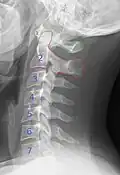

Cervical lines are annotations used in medical imaging of the cervical vertebrae, here seen on X-ray and CT, respectively. Incongruencies indicate cervical fracture, spondylolisthesis and/or ligament injury.

Cervical degenerative changes arise from conditions such as spondylosis, stenosis of intervertebral discs, and the formation of osteophytes. The changes are seen on radiographs, which are used in a grading system from 0–4 ranging from no changes (0) to early with minimal development of osteophytes (1) to mild with definite osteophytes (2) to moderate with additional disc space stenosis or narrowing (3) to the stage of many large osteophytes, severe narrowing of the disc space, and more severe vertebral end plate sclerosis (4).[5][6][7]